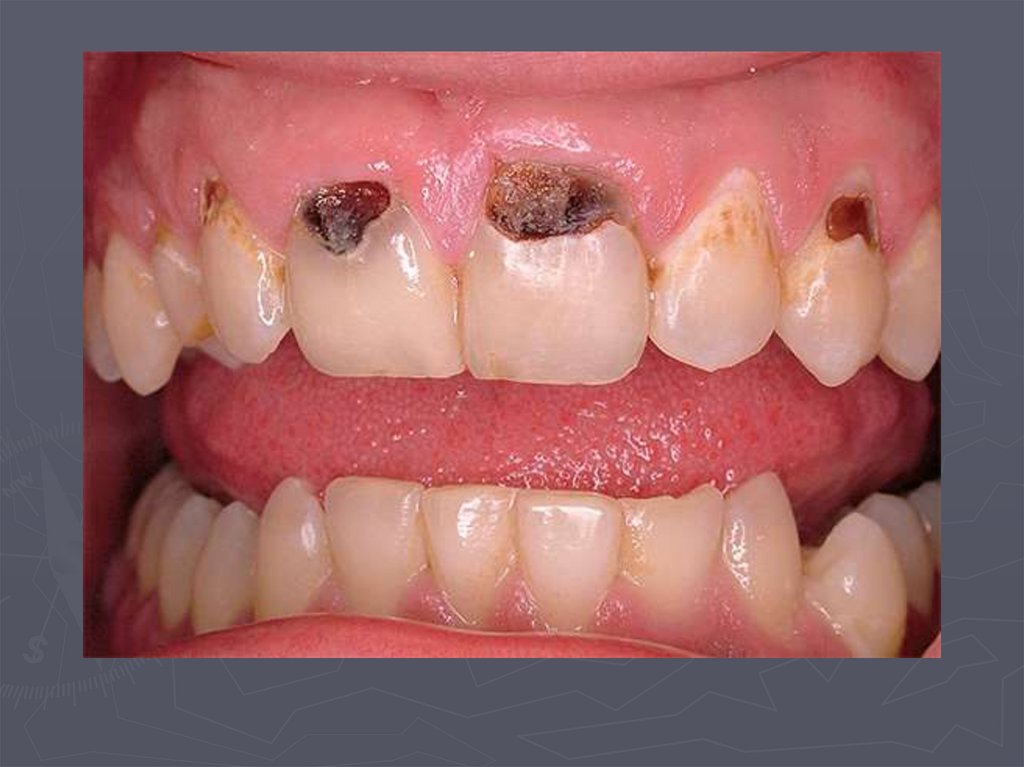

4. ОСОБЕННОСТИ КЛИНИЧЕСКОГО ПРОЯВЛЕНИЯ КАРИЕСА У ДЕТЕЙ РАННЕГО ВОЗРАСТА

У детей в возрасте от 1года до 3 лет КАРИЕС

чаще возникает:

► на зубах, имеющих порочно развитые ткани в виде

гипоплазии;

► ткани этих зубов недостаточно минерализованы;

► чаще поражаются резцы;

► затем моляры и клыки;

► преимущественная локализация кариозной полости на

вестибулярной и контактной поверхности резцов ;

► а также в фиссурах моляров;

► нередко кариес начинается в пришеечной области;

► процесс распространяется вокруг всей коронки;

► формируется циркулярный кариес.

8. Циркулярный кариес